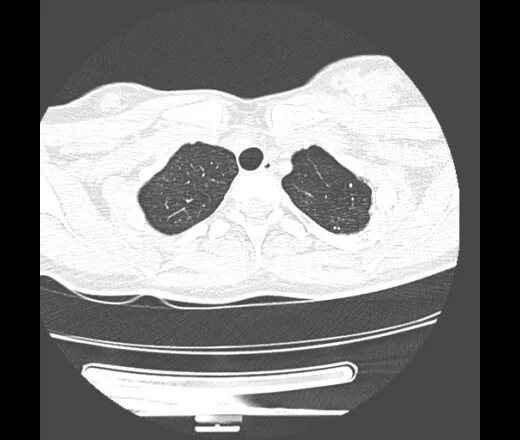

Метатуберкулезные изменения в легких что это означает